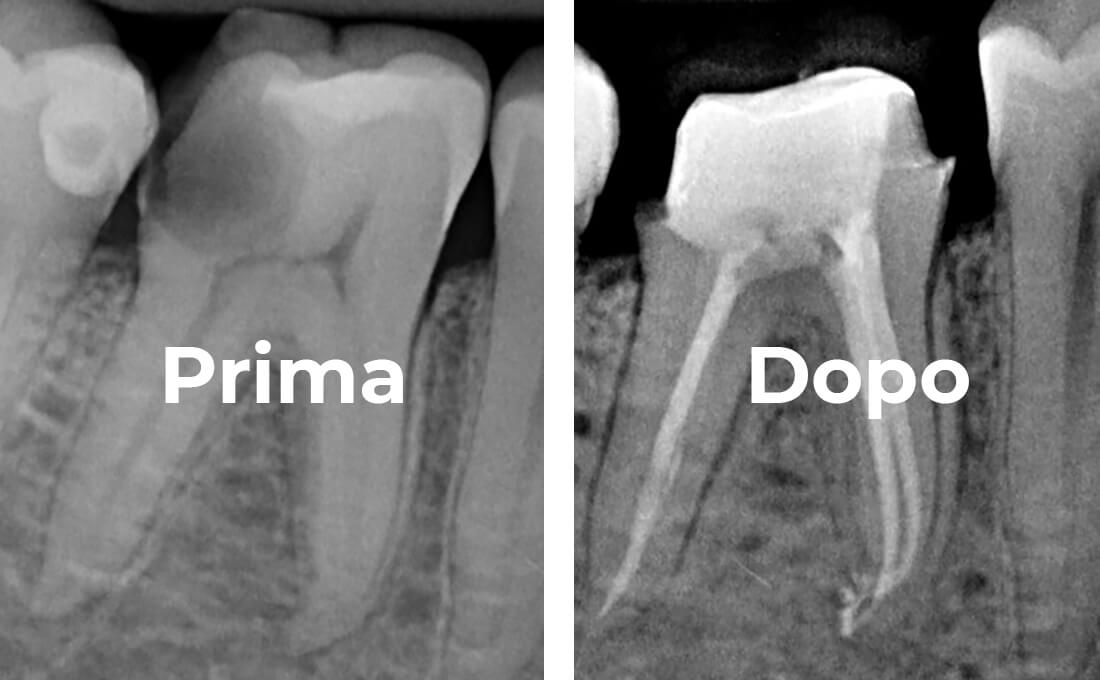

Radiologia 2D e 3D

Cone Beam

Ai fini della diagnostica e quindi del successo terapeutico, direttamente nei nostri studi